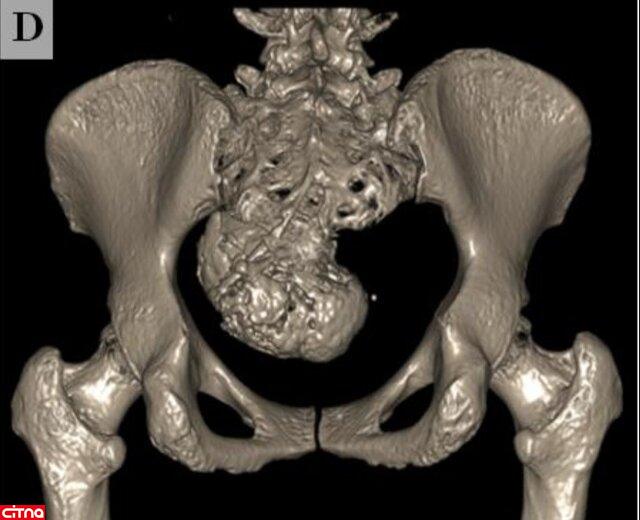

گزارش مورد نادر «جنین سنگی» در یک زن ۵۲ ساله ایرانی

در پی یافتن اتفاقی یک جنین سنگی در بدن یک زن ۵۲ ساله، گزارش این مورد نادر در یک مجله علمی بین‌المللی منتشر شد.

به گزارش ایسنا، «لیتوپدیون» یا جنین سنگی یکی از عوارض بسیار نادر حاملگی‌های خارج رحمی است که به صورت توده کلسیفیه در قسمتی از حفره شکم یا لگن ظاهر می‌شود. کلسیمی شدن یا کلسیفیکاسیون رسوب کلسیم در بافتی از بدن است.

در لیتوپدیون یا جنین سنگی، پس از لقاح، جنین خارج از رحم تشکیل می‌شود ولی به دلیل این‌که شرایط برای رشد آن مناسب نیست، پس از مدتی رشد متوقف می‌شود و شروع به کلسیمی شدن می‌کند. معمولاً فرد از وجود جنین سنگی در بدن خود مطلع نمی‌شود و سال‌ها بعد به صورت اتفاقی وجود آن مشخص می‌شود.

این یک پدیده نادر است که در ۱.۵ تا ۲ درصد از حاملگی‌های خارج از رحم ودر  ۰.۰۰۵۴ درصد از تمام حاملگی‌ها رخ می‌دهد.

اخیراً به صورت اتفاقی یک جنین سنگی از بدن یک زن ۵۲ ساله در ایران خارج شده و گزارش این اتفاق در مجله «Radiology Case Reports» منتشر شده است.

عضو گروه رادیولوژی بیمارستان شهید ستاری دانشگاه علوم پزشکی شهید بهشتی در مورد خارج کردن جنین سنگی از یک خانم ۵۲ ساله در ایران توضیح داد: در این مورد که اخیراً گزارش شده است، یک بیمار ۵۲ ساله به دنبال تصادف، به اورژانس مراجعه می‌کند. با یک عکس ساده لگن پزشکان متوجه وجود یک توده در بدن فرد می‌شوند و توده از طریق جراحی از بدن فرد خارج می‌شود. بر اساس بررسی‌های انجام‌شده، مشخص می‌شود که این توده «لیتوپدیون» یا جنین سنگی است.